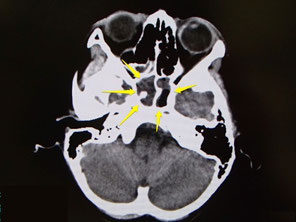

頭痛が主訴であった。鼻の奥の上咽頭がんの患者さんです。

上咽頭癌では、頭の芯や後頭部の痛みを訴えられることがあります。